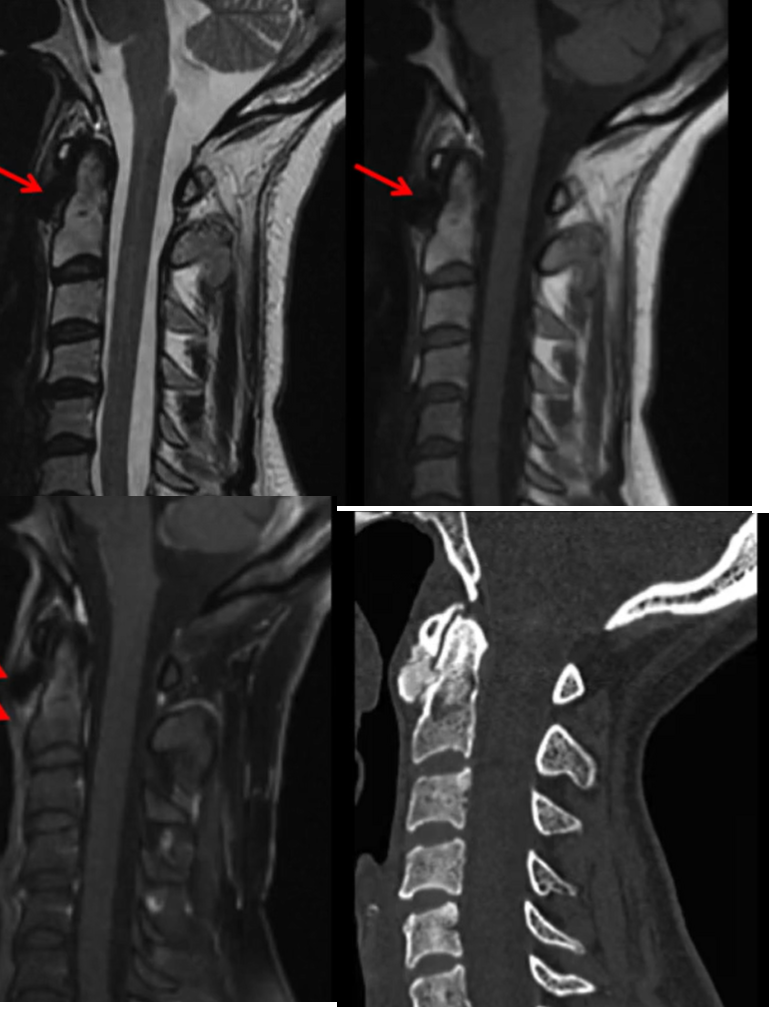

Paciente de 72 anos com quadro de cervicalgia subaguda. Apresenta nos exames de imagem o seguinte achado.

Qual o diagnóstico?

Pode ser um achado fisiológico esta imagem?

Metástase na coluna cervical